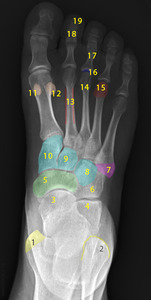

Two unlabeled illustrated images, figures 1 and 2, of the foot and one unlabeled x-ray image, figure 3, were selected. Each image was inputted into ChatGPT Version 4o and the model was prompted to identify the bones depicted in each image using the following prompt.

Prompt 2: ‘Identify the structures labeled in this image’

Prompt 2: Identify the structures labeled in this image

Out of 19 labels, 19 were identified correctly, resulting in an accuracy of 0%.